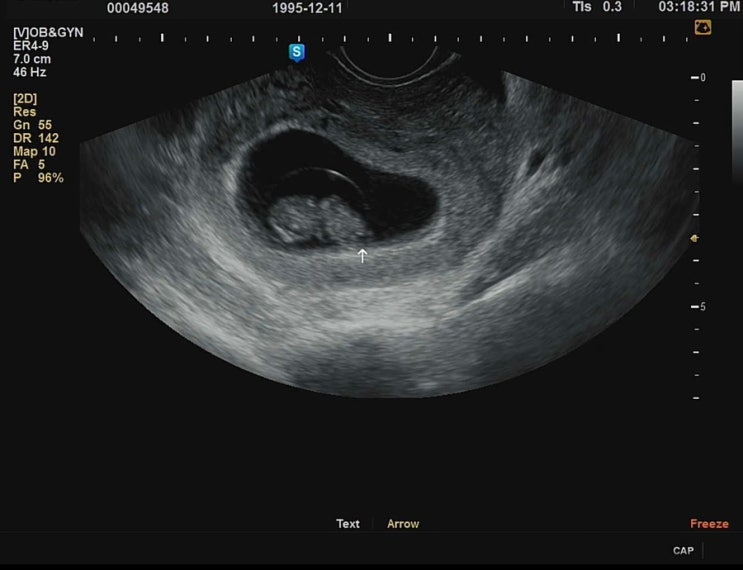

임신 12주) 1차 기형아 선별 검사, 각도법 성별 유추

사실은 11주 6일에 진행한 1차 기형아 선별 검사인데 어차피 하루 차이니까 편의상 12주라고 하겠다! 12주...